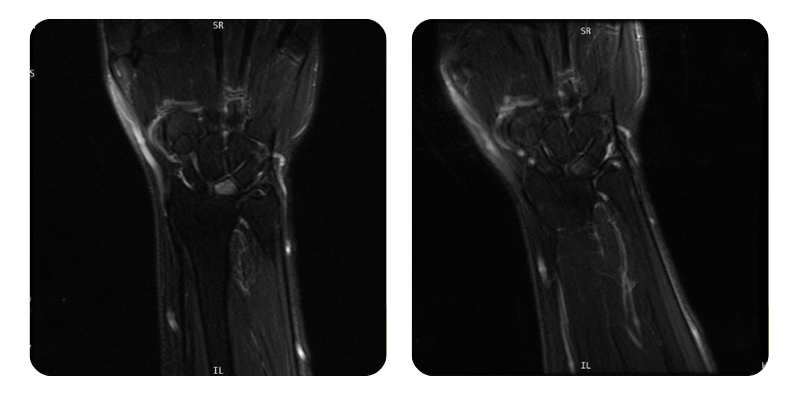

Prima

Dopo

B.A.A., 54 anni - Osteonecrosi avascolare del semilunare sinistro

Risultati: Risonanza magnetica della mano.

Diagnosi: Osteonecrosi avascolare del semilunare sinistro, ipertensione arteriosa, ipotiroidismo.

Evoluzione: Dopo 20 sedute di ossigenoterapia iperbarica, la paziente presenta una remissione di circa l'80%, con scomparsa completa del dolore alla mano sinistra. Non si rilevano più limitazioni funzionali e ha ripreso l'attività abituale senza disagio.